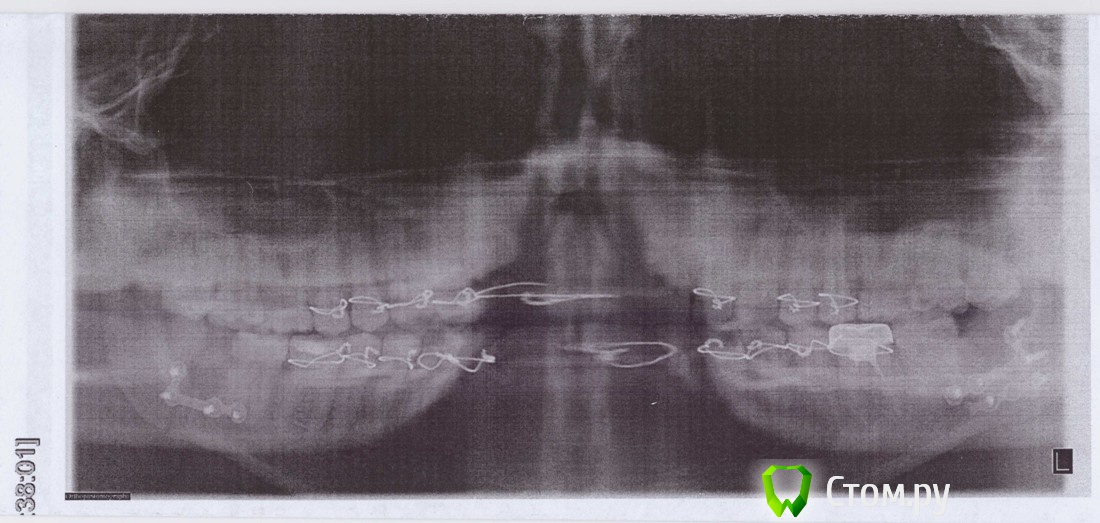

ivanich 82 Опубликовано 27 июня, 2014 Поделиться Опубликовано 27 июня, 2014 Доброго времени суток. Помогите разобраться в такой ситуации: у меня случился двусторонний перелом нижней челюсти со смещением отломков, время было вечер пятницы в "приемнике" мне сделали снимок и направили в городскую стоматологию, там хирургов уже не было, перевязали челюсть повязкой и на утро на прием. Еле дожил до утра, на прием, сделали еще снимки, хирург сказал наложим шины и удалим два зуба в местах переломов. Удалил зуб мудрости и с другой стороны зуб, по-моему, №38, шинировал и направил на операцию. В другом городе сделали операцию. Спустя лишь сутки, при смене повязки, вспомнили, что надо шины стянуть резиновыми тягами. Через неделю сняли швы и до свидания. Кололи какие-то антибиотики, обезболивали, анальгином, спать почти не мог, ну ладно не суть. Итог два шва ни лице. Прибыл домой, на прием, ходил две недели, поменяли резиновые тяги, делали снимки, прошел 21 день с момента операции, сняли тяги, в пятницу на прием, сказал снимет шины. Но сейчас обнаружил, к ужасу, шатающиеся зубы, искривился прикус, челюсти не совпадают, нижняя уехала вперед и по-моему вбок, но на снимках вроде все ровно в местах переломов. Подскажите, что делать с шатающимися зубами, как их спасти, здоровые же зубы, что делать с прикусом, как разработать челюсть, жевать не могу, ужасно болят зубы и не открывается полноценно рот. Я в шоке, челюстно-лицевой хирург, делавший операцию, мне кажется, искренне ждал денег, платить не стал, соответственное и лечение получил. Осмотр у меня врачом занимал максимум минуту: "Как дела?", все пройдет, надо время и т.п. Такой же мне кажется и хирург, к которому я хожу дома, зачем я хожу с шинами, которые не фиксированы тягами, проволока рвет уже десны, одна лигатура уже лопнула и с ужасом ожидаю пятницу, разорвет наверное весь рот. Купил полоскание под названием: "Стоматофит" и пью "КАльцевит", что делать дальше??? Сегодня пятница, на приеме у хирурга долго смотрел на челюсть и ему не понравилось, что она "выехала" вперед, спрашивает: "А тяги порвались и Вы их сами сняли?", я глаза вытаращил и говорю: "Доктор, Вы же сами мне их в понедельник сняли, сказали челюсть разрабатывай". Он хмыкнул и говорит: "Быть может неправильно сделали операцию и неправильно закрепили пластины, езжайте вновь на консультацию в ту больницу (200 км.) и быть может понадобится новая операция". Я в таком шоке, не передать, помогите, пожалуйста. Прилагаю снимок на следующий день после травмы, после выписки после операции и фото как сейчас выглядит челюсть, все остальные снимки в карточке. Ссылка на комментарий

ivanich 82 Опубликовано 28 июня, 2014 Автор Поделиться Опубликовано 28 июня, 2014 Доброго времени суток. Помогите разобраться в такой ситуации: у меня случился двусторонний перелом нижней челюсти со смещением отломков, время было вечер пятницы в "приемнике" мне сделали снимок и направили в городскую стоматологию, там хирургов уже не было, перевязали челюсть повязкой и на утро на прием. Еле дожил до утра, на прием, сделали еще снимки, хирург сказал наложим шины и удалим два зуба в местах переломов. Удалил зуб мудрости и с другой стороны зуб, по-моему, №38, шинировал и направил на операцию. В другом городе сделали операцию. Спустя лишь сутки, при смене повязки, вспомнили, что надо шины стянуть резиновыми тягами. Через неделю сняли швы и до свидания. Кололи какие-то антибиотики, обезболивали, анальгином, спать почти не мог, ну ладно не суть. Итог два шва ни лице. Прибыл домой, на прием, ходил две недели, поменяли резиновые тяги, делали снимки, прошел 21 день с момента операции, сняли тяги, в пятницу на прием, сказал снимет шины. Но сейчас обнаружил, к ужасу, шатающиеся зубы, искривился прикус, челюсти не совпадают, нижняя уехала вперед и по-моему вбок, но на снимках вроде все ровно в местах переломов. Подскажите, что делать с шатающимися зубами, как их спасти, здоровые же зубы, что делать с прикусом, как разработать челюсть, жевать не могу, ужасно болят зубы и не открывается полноценно рот. Я в шоке, челюстно-лицевой хирург, делавший операцию, мне кажется, искренне ждал денег, платить не стал, соответственное и лечение получил. Осмотр у меня врачом занимал максимум минуту: "Как дела?", все пройдет, надо время и т.п. Такой же мне кажется и хирург, к которому я хожу дома, зачем я хожу с шинами, которые не фиксированы тягами, проволока рвет уже десны, одна лигатура уже лопнула и с ужасом ожидаю пятницу, разорвет наверное весь рот. Купил полоскание под названием: "Стоматофит" и пью "КАльцевит", что делать дальше??? Сегодня пятница, на приеме у хирурга долго смотрел на челюсть и ему не понравилось, что она "выехала" вперед, спрашивает: "А тяги порвались и Вы их сами сняли?", я глаза вытаращил и говорю: "Доктор, Вы же сами мне их в понедельник сняли, сказали челюсть разрабатывай". Он хмыкнул и говорит: "Быть может неправильно сделали операцию и неправильно закрепили пластины, езжайте вновь на консультацию в ту больницу (200 км.) и быть может понадобится новая операция". Я в таком шоке, не передать, помогите, пожалуйста. Прилагаю снимок на следующий день после травмы, после выписки после операции и фото как сейчас выглядит челюсть, все остальные снимки в карточке. Пожалуйста! Помогите с моей ситуацией, ответьте, знающие люди!!!!!!!!! Ссылка на комментарий